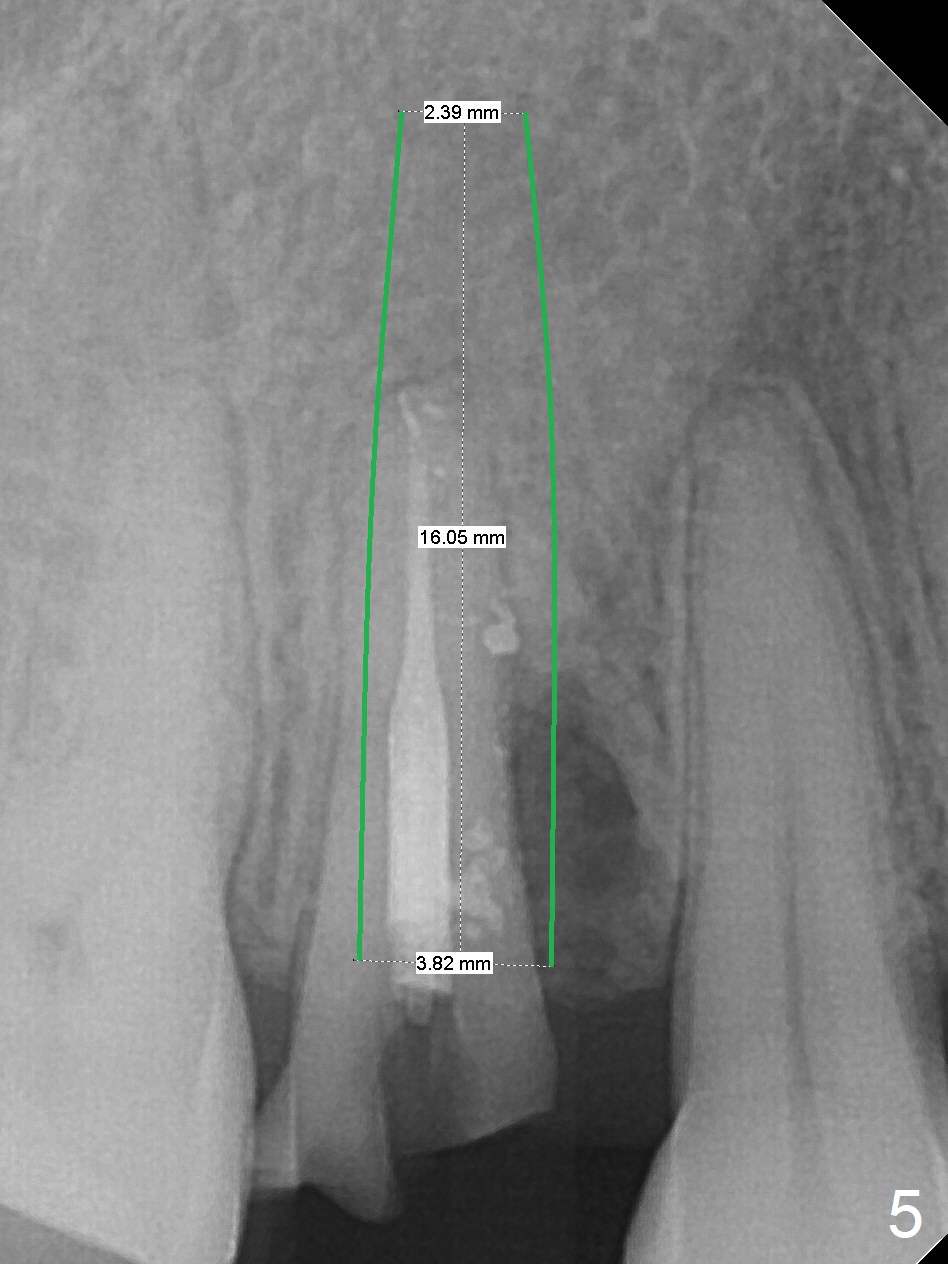

Seven years post RCT (Fig.1), the tooth #4 of a 65-year-old woman fractures subgingival palatally (Fig.2).  Since the root of the affected tooth is close to the tooth #3, osteotomy is established in the mesial slope of the socket (Fig.3).  Change the trajectory once the drill has penetrated the lamina dura of the socket (Fig.4).  The initial depth will be 20 mm for a 3.8x16 mm implant (Fig.5).